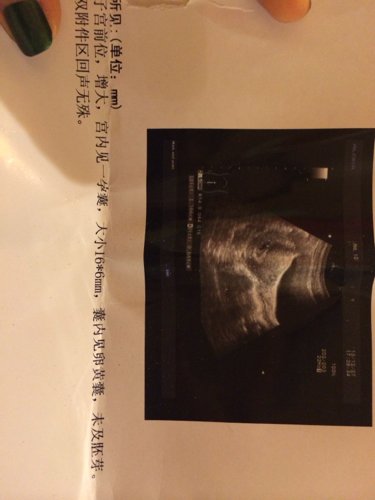

和男朋友四号在一起过 然后就没来月经了 这个大概多少天了 还要过多久才能做人流呢? 点击展开 匿名用户 2013-12-28 20:02 为您推荐: 其他回答 病情分析: 根据你所描述的情况,算怀孕的天数是根据月经周期算的, 指导意见: 你好,您是那天来的月经,现在你的比超报告的输液40天左右的孕囊,没有胎芽的,如果您不要孩子,只要子宫里看到孕囊就可以做人流术的, 匿名用户 2013-12-28 20:47 相关问题 我才17岁,和男朋友在一起不小心怀孕了,他妈妈一定要我把孩子生下来 当时我们没钱做人流,我也不敢和 如果你做人流时你男朋友什么也没说也不陪你你还会跟他在一起吗 我刚做人流半个月就和男朋友在一起了也没有什么不舒服的,就是之前就有点味道流黄的东西怎么办